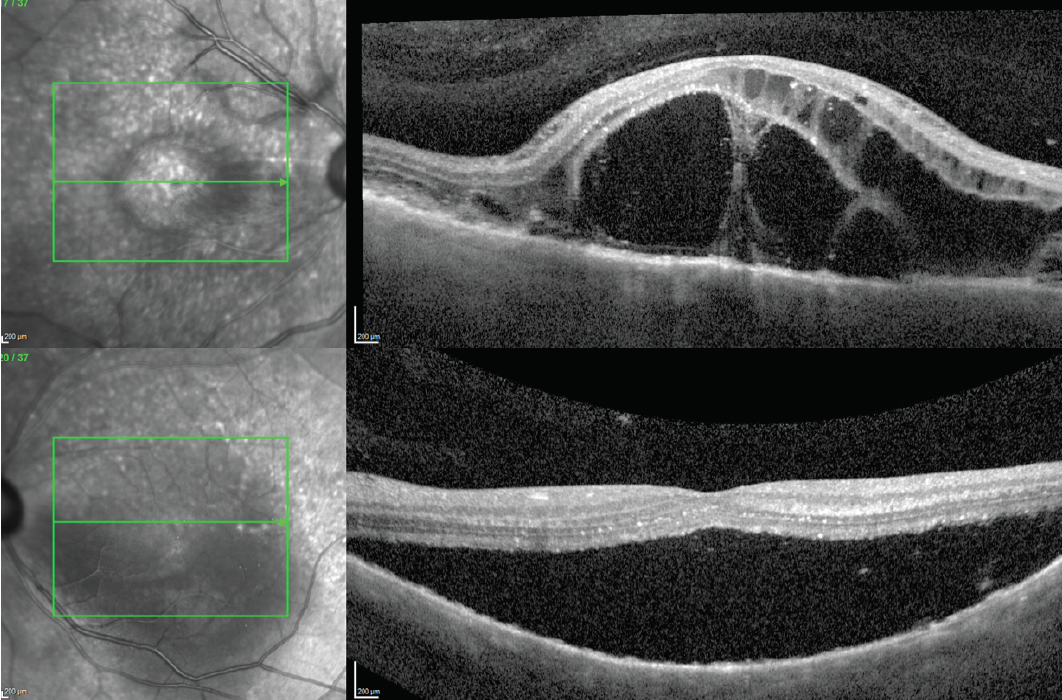

Imaging with spectral-domain OCT (SD-OCT) showed subretinal fluid with sub–external limiting membrane fluid in the right eye and subretinal fluid in the left eye (Figure 2). Fluorescein angiography revealed multifocal pinpoint leakage in the posterior pole in both eyes (Figure 3) without evidence of disc leakage.

<p>Figure 2. OCT of the right eye (top) demonstrates extensive intraretinal cystic fluid. OCT of the left eye (bottom) demonstrates subretinal/subexternal limiting membrane fluid.</p>

Figure 2. OCT of the right eye (top) demonstrates extensive intraretinal cystic fluid. OCT of the left eye (bottom) demonstrates subretinal/subexternal limiting membrane fluid.

Our patient was initially thought to have VKH, given his bilateral exudative retinal detachments with subretinal septa in his right eye on OCT, as well as fluorescein angiography showing multifocal macular leakage in both eyes. The patient also had a dome-shaped mass of intraretinal fluid, termed a bacillary detachment, which is commonly seen in patients with VKH. Of note, our patient did not have optic nerve leakage on fluorescein angiography, which is often seen in VKH.